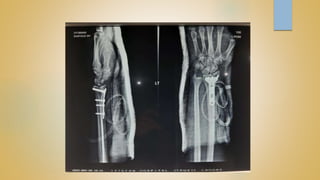

 OPERATIVE

CLOSED REDUCTION AND PERCUTANEOUS K-WIRING

OPEN REDUCTION AND INTERNAL FIXATION

EXTERNAL FIXATOR APPLICATION